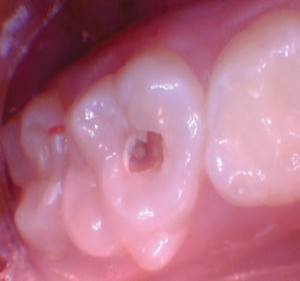

Figura 2. La exposición pulpar se produjo al excavar la dentina infectada (la exposición pulpar no se capturó en la foto). |

Figura 4. Después de excavar el tejido pulpar en los orificios del canal, se utilizó una prenda de algodón seco para evaluar la salud de la pulpa mediante la aplicación de hemostasia por presión. |